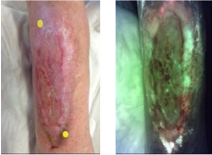

Skin Pigmentation Impacts the Clinical Diagnosis of Wound Infection: Imaging of Bacterial Burden to Overcome Diagnostic Limitations

Johnson J. et al. JREHD 2023